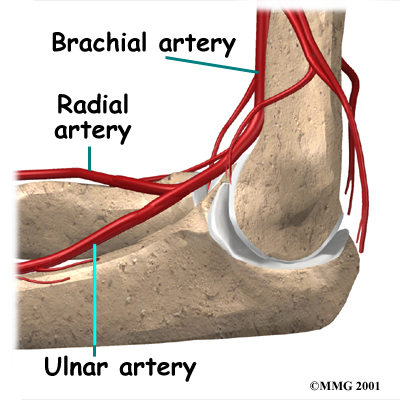

Blood Vessels

Traveling along with the nerves are the large vessels that supply the arm with blood. The largest artery is the brachial artery that travels across the front crease of the elbow. If you place your hand in the bend of your elbow, you may be able to feel the pulsing of this large artery. The brachial artery splits into two branches just below the elbow: the ulnar artery and the radial artery which both continue into the hand. Damage to the brachial artery can be very serious because it is the only blood supply to the hand.